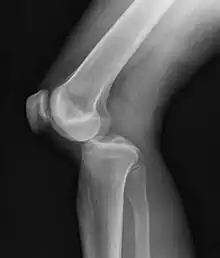

| Plain lateral X-ray of the left knee showing a posterior knee dislocation[1] | |

Plain X-rays, CT scan, ultrasonography, or MRI may help with the diagnosis.[2][11] Findings on X-ray that may be useful among those who have already reduced include a variable joint space, subluxation of the joint, or a Segond fracture.[5]